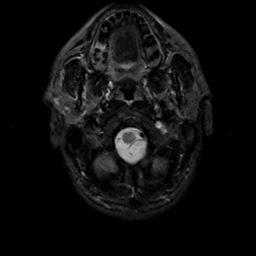

MR Study #6, March 17, 1991 -- Slice #2

[Home][Help][Clinical][Tour 1][Tour 2] Slice 2